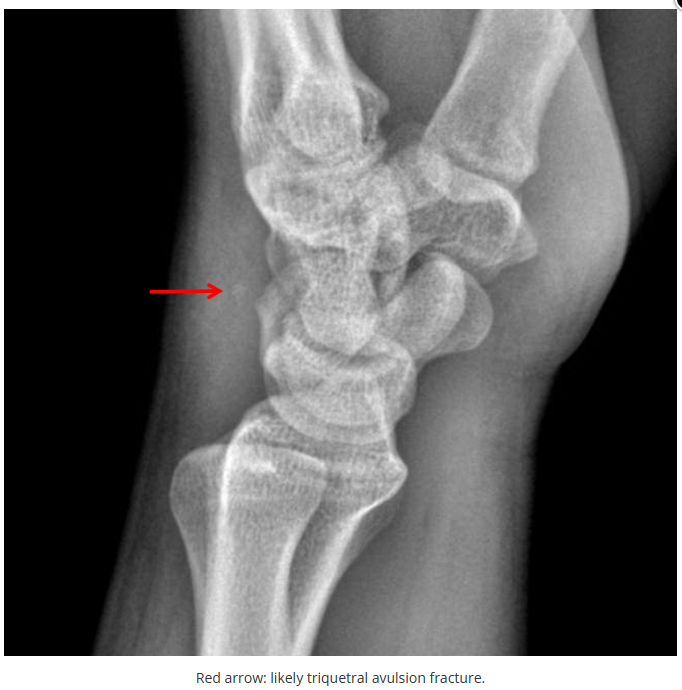

这些腕与手的骨折X线片如果没有标注箭头,你还能识别出来吗?

X线读片是骨科医生的基本功。

今天是腕部与手的X线片。所有X线片都

带有标注和说明

,可以选择长按图片,

自动翻译相关说明